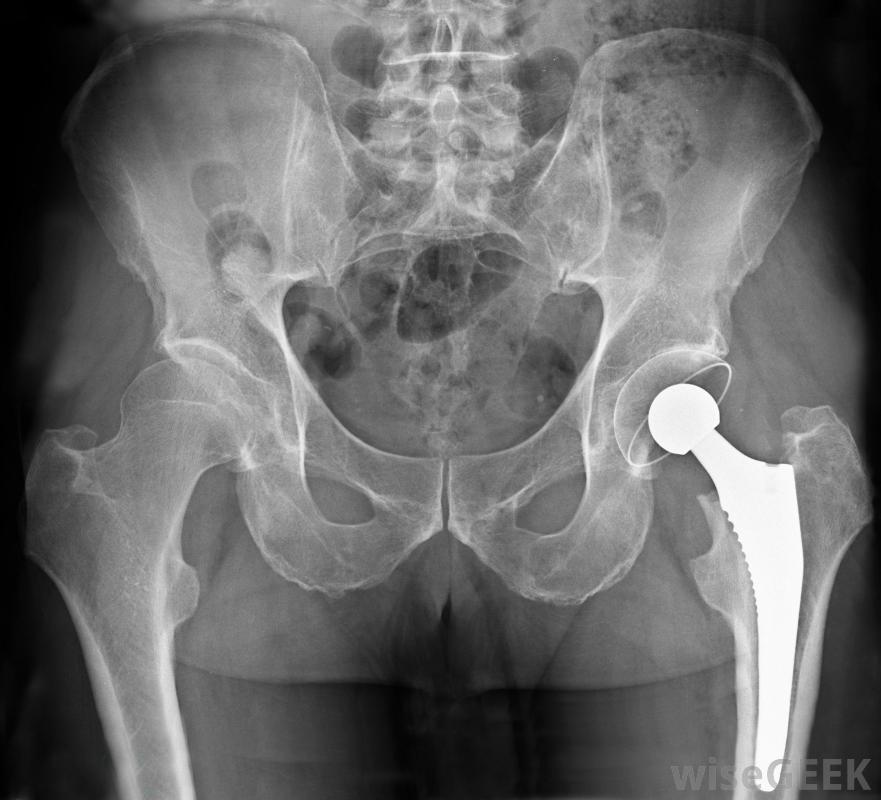

严重的髋关节应力性骨折可能需要髋关节置换手术来修复。

根据髋部应力性骨折的严重程度,可能需要手术来促进愈合过程。如果应力性骨折是某种物理创伤(如事故)的结果,则尤其如此。手术可以让医护人员直观地评估损伤,帮助将碎片重新对齐,并可能安装销钉或其他装置,以帮助减轻受损区域的应力。如果损伤特别严重,可能需要进行髋关节置换手术。